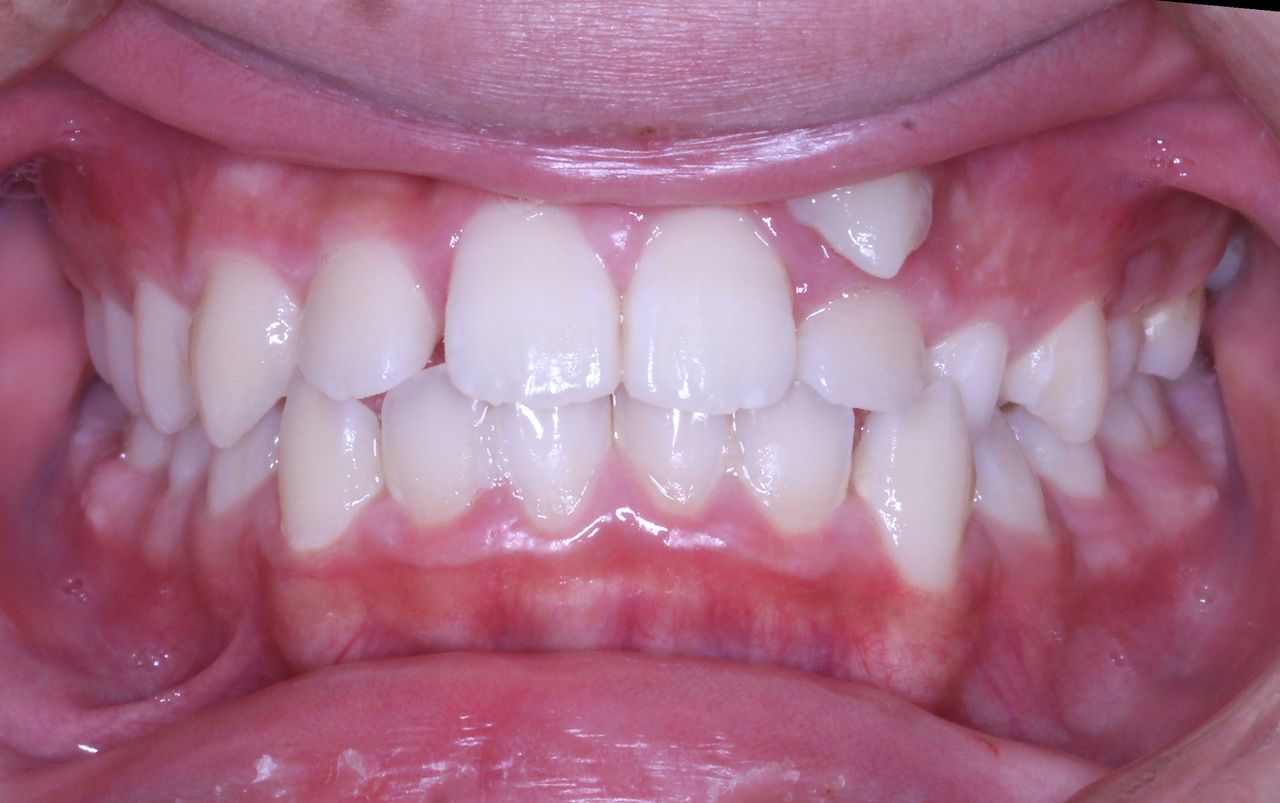

それでは治療開始前の状態です

このように1番目と2番目の歯の間から犬歯3番目の歯が生えてきました。

また乳歯Cが残っているので 歯の順番でいうと

132Cという順番になっております